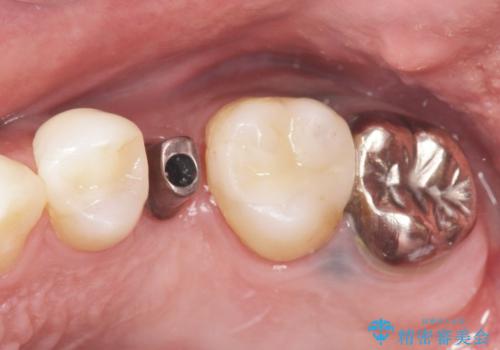

骨の厚みが不足していたため、インプラントの埋入と同時にソケットリフト(上顎骨に骨を増やす手術)を行いました。

インプラントの種類:ストローマン BLT

被せ物の種類:オールセラミッククラウン スタンダード